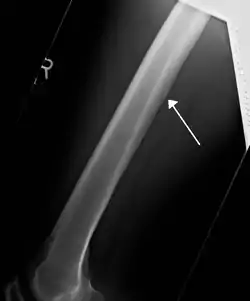

![]() صورة الأشعة السينية تبين النفق المغذي للعظم في عظم الفخذ مُشار إليه بالسهم الأبيض. صورة الأشعة السينية تبين النفق المغذي للعظم في عظم الفخذ مُشار إليه بالسهم الأبيض. | |